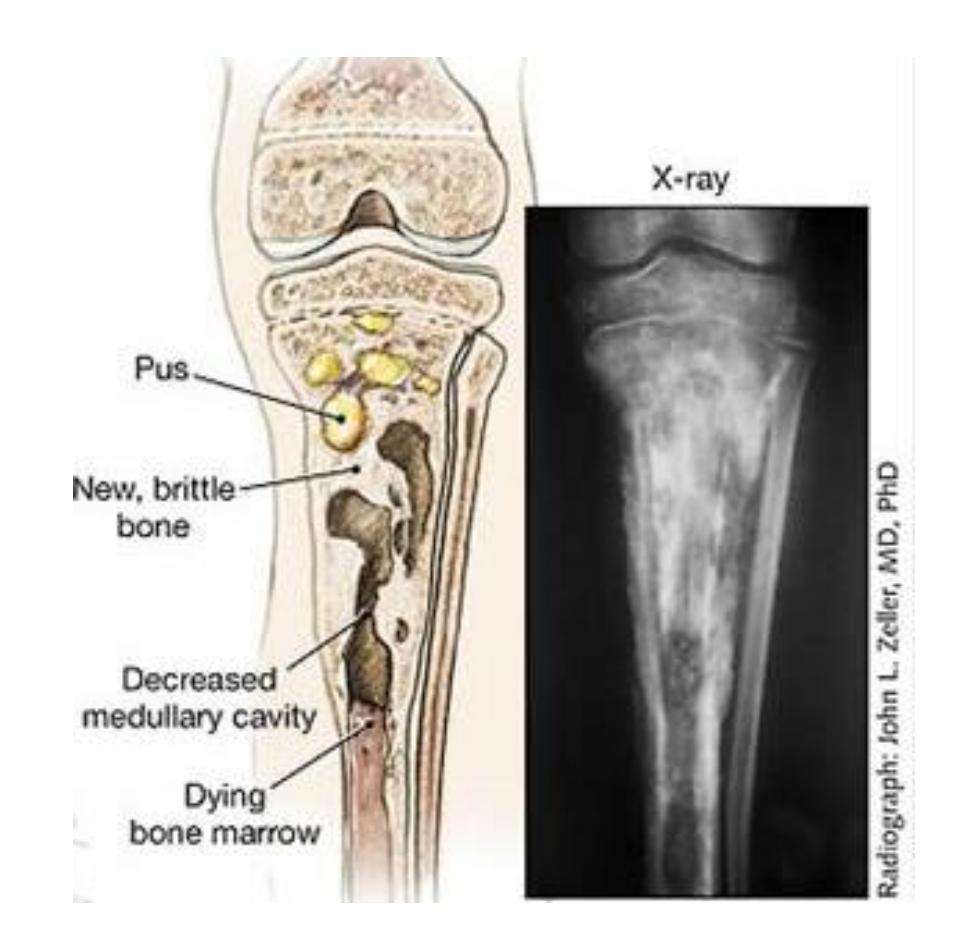

Osteomyelitis

What anatomical structure is indicated by the blue arrow in a patient with chronic osteomyelitis?

- a. Involucrum

16- The blue arrow show?

A. Involucrum

What are the characteristic findings and diagnosis for a 7-year-old with painful swollen lower thigh and recurrent fever?

Q1: Abnormal x-ray findings:

- Cavitation

- Periosteal reaction

- Involucrum

- Sequestration

Q2: Diagnosis:

- Chronic osteomyelitis

Chronic Osteomyelitis

Radiological Features

- Rarefaction surrounded by sclerosis

- Cavities and sequestra

Key Pathological Features

- Sequestrum: Dead bone fragment that becomes separated from healthy bone

- Involucrum: New bone formation surrounding the sequestrum

- Cavitation: Bone destruction forming cavities

- Sinus formation: Draining tracts to skin surface